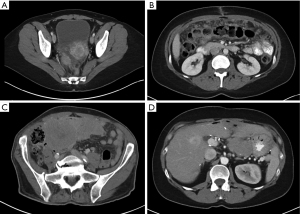

Computed tomography (CT) is the principal imaging modality utilized for diagnosis. While positron emission tomography (PET) can be used in conjunction with CT, its value in initial diagnosis is not clear (20). Radiographically, the disease may present as mesenteric or parietal peritoneal nodules, visceral peritoneal thickening leading to foreshortening of the mesentery, ascites, or omental masses (21). Favorable radiographic findings include minimal soft tissue masses, normal intestine and mesenteric anatomy, and lack of ascites. Unfavorable findings include tumors >5 cm, especially tumors involving the lesser omentum or jejunal regions; para-aortic lymphadenopathy, and diffuse peritoneal thickening resulting in anatomic distortion of the bowel (8,22,23). A hallmark feature of MPM is its propensity to remain confined to the abdominal cavity. In fact, extra-abdominal disease is rare and typically only manifests by direct disease extension from the diaphragm across into the pleural space or via extra-abdominal lymph node metastasis (11,24) (Figure 1).